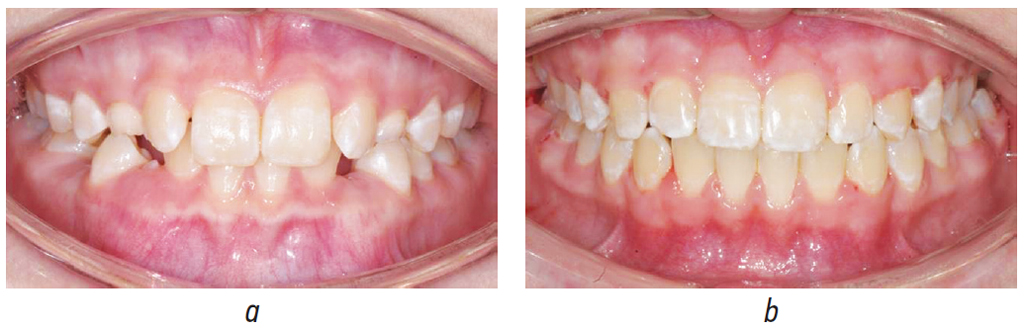

CLINICAL CASE. PATIENT WITH ENAMEL HYPOPLASIA BEFORE AND AFTER TREATMENT

Patient M, a 15-year-old girl, was diagnosed with mesial occlusion, retention of teeth 4.3 and 3.3, postnatal systemic enamel hypomineralization, and celiac disease (gluten enteropathy), as shown in Figure 3.

Fig. 3. Patient M.’s teeth before (a) and after (b) treatment

Рис. 3. Фотографии зубов пациента М. до (а) и после (b) лечения

Before bracket system placement, the decayed/missing/filled teeth (DMF) index was 4, the TER value was 44%, the hygiene index was 58%, and noncarious spots were present in 24%. The treatment period was 25 months. After removing the bracket system, the DMF index was 5. The TER-test value and the hygiene index were 46% and 43%, respectively. In addition, noncarious spots were observed in 24% of the cases.